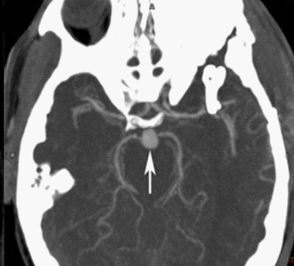

我們使用CT或MRI造影,都能發現動脈瘤的存在。下圖這個箭頭指的圓圓的、和周圍血管不一樣的地方就是動脈瘤。

CTA提示基底動脈尖動脈瘤 圖源:WestJEM